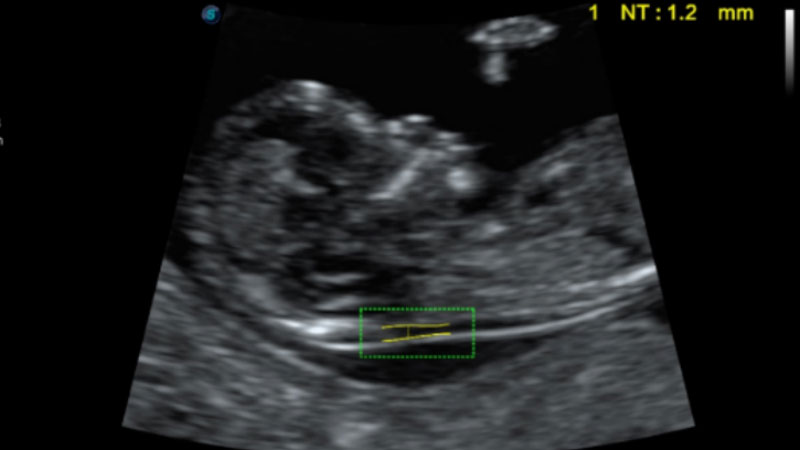

S-Fetus基于大数据深度学习算法,能够帮助您在产前筛查过程中智能识别胎儿标准切面、自动测量并录入报告。一个按键,即可智能、精准、高效地获取胎儿生理指标,极大简化您的产科检查操作。

可快速对产科扫查切面完成胎儿生理学参数的自动测量,减少操作者按键次数,大幅提升检查效率。

自动识别颈项透明层并获得NT值,为早孕胎儿畸形筛查提供有效测量工具,提高诊断效率和诊断信心。